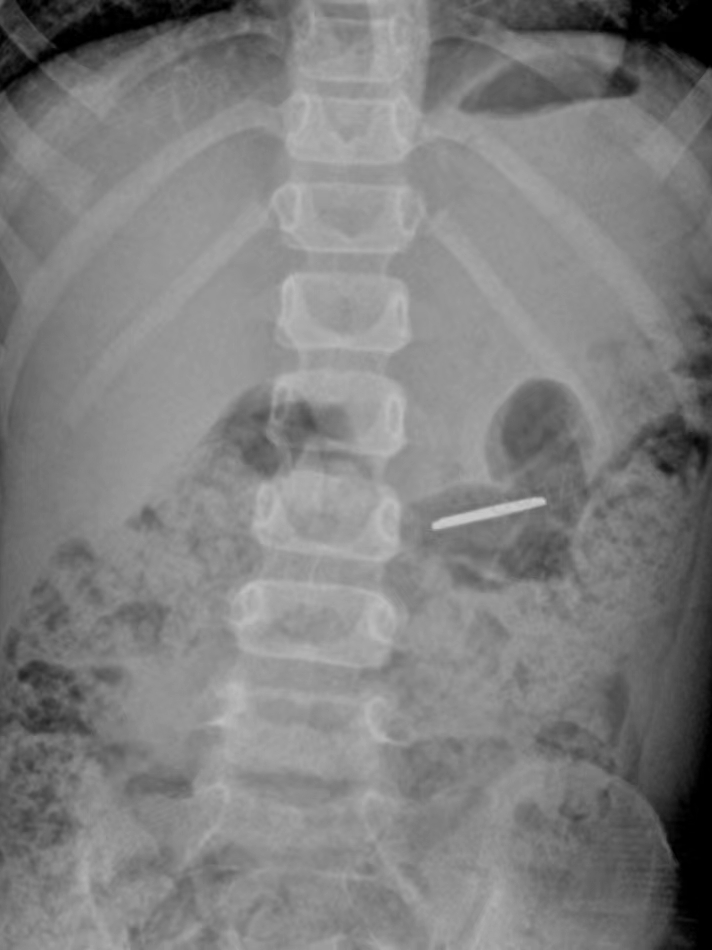

2023年11月27日晚上10時(shí),一名4歲女童誤吞一枚紐扣電池,女童的家屬發(fā)現後(hòu),心急如焚地將(jiāng)女童送至惠州六院急診醫學(xué)科,經(jīng)過(guò)腹部拍片檢查,醫務人員懷疑異物位于孩子的左上腹,不排除異物位于消化道(dào)的可能(néng)。

在無痛胃鏡的幫助下,手術團隊在小女孩的胃裡(lǐ)找到了那個硬币大小(直徑約1.5cm)的電池,卡在了幽門口,還(hái)好(hǎo)沒(méi)有進(jìn)入小腸。

在就(jiù)診過(guò)程中可能(néng)需要做X線平片檢查、CT檢查或超聲檢查等影像學(xué)檢查,以及血常規、凝血功能(néng)、感染相關疾病檢查等實驗室檢查,醫生會(huì)根據檢查情況采取随診觀察、内鏡手術或外科手術等治療手段。